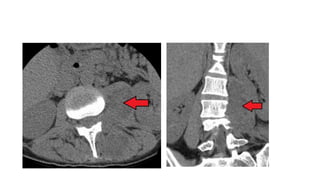

A) Axial T2 MRI image showing the psoas muscle (red arrow) and facet joint lesion spreading to

multifidus muscle (blue arrow). (B) Coronal T1 MRI post gadolinium showing extensive psoas

muscle abscess (red arrow).

MR is more sensitive than CT in diagnosis of intra-abdominal abscesses.

MRI ● Magnetic resonanceimaging (MRI) may allow improved definition of soft tissues and adjacent structures, especially visualization of the vertebral bodies. ● Evidence of bony spinal infection : suspicion for tuberculosis in the appropriate epidemiologic circumstances. ● Advantage: better discrimination of soft tissues and the ability to visualise the abscess wall and the surrounding structures without the need of a intravenous contrast medium

A) Axial T2MRI image showing the psoas muscle (red arrow) and facet joint lesion spreading to multifidus muscle (blue arrow). (B) Coronal T1 MRI post gadolinium showing extensive psoas muscle abscess (red arrow). MR is more sensitive than CT in diagnosis of intra-abdominal abscesses.